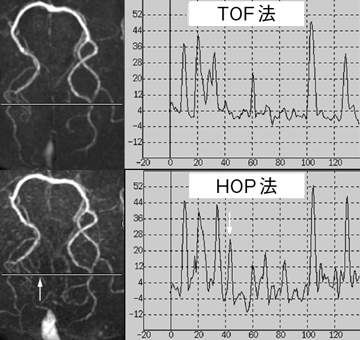

図5 HOP-MRAとTOFのシグナル・プロファイリングカーブの比較

PCA末梢血管CNRは,TOF法に比べHOP法で増大している。

縦軸は背景に対するCNR=(S-Sback)/noiseSDを表す。